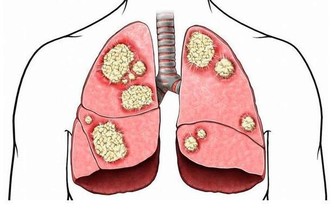

大腸癌也會導致慢性腹瀉,但可能不全是腹瀉,也可能表現為腹瀉和便秘反復交替發生。

每天多喝水,適當多吃含植物纖維較多的食物,如新鮮蔬菜、水果。這不僅可以防止便秘,還能降低腸道惡性疾病(如結腸癌)的發生。